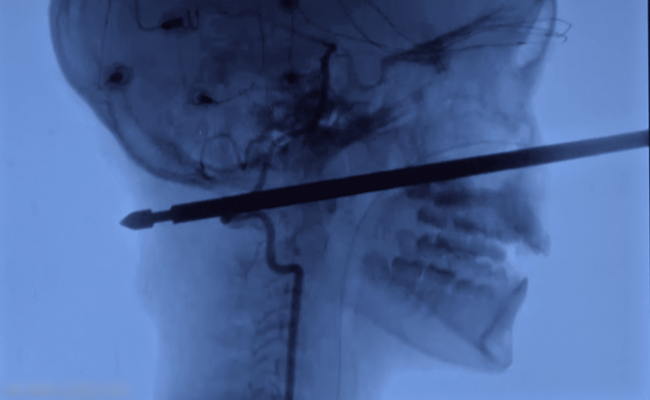

بدأ صبي أمريكي (عشر سنوات) في التعافي بعد أن هاجمته حشرات وتعثر وسقط من فوق شجرة ليسقط فوق سيخ لحم، اخترق جمجمته من الأمام للخلف.

لكن المعجزة حدثت عندما انتهى حظ الصبي خافيير كننينغهام العاثر، ذلك أن السيخ لم يصب عين اكزافييه أو مخه أو حبله الشوكي، أو أوعيته الدموية الرئيسية ، حسبما أفادت صحيفة “كانساس سيتي ستار”.

الفتى سقط على الأرض ونزلت أمه غابرييل ميللر السلم مسرعة عندما سمعت الصراخ، وبحسب ما اوردت قناة “سكاي نيوز”، السيخ الحديدي الذي يبلغ طوله أكثر من 15 سنتيمترا، ثقب رأسه من الأمام للخلف ولا يزال يطل بارزا من وجهه.

وقال إيبرسول “لا يمكنك أن تثقب بدقة أفضل… احتمال واحد في المليون أن تخترق خمسا إلى ست بوصات من مقدمة الوجه لمؤخرته دون أن تصيب هذه الأشياء”.

ولأن السيخ كان مربعا بأطراف حادة كان يتعين أن يخرج بشكل مستقيم تماما، فأي انحراف كان من شأنه أن يؤدي إلى إحداث ضرر أكبر.